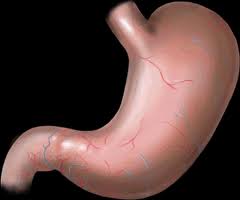

-İçki mideye zarar verir

Son yapılan bir araştırmaya göre içkinin mideye olumsuz etki yaptığı görülmüş, sümüksü tabakanın kanlanmasına, su minerallerin bozulması ile vücuttaki asitlerin fazlaca dışarı atılması sonucunda midede tehlikeli yaralar meydana getirdiği tesbit edilmiştir. Bu durum daha da ilerleyerek mide kanserine yol açabilir. Aynı şekilde alınan alkollü içeceklerden bağırsaklar da kötü etkilenip bağırsaklarda da tehlikeli iltihaplanmalar meydana gelir. Aynı şekilde midenin emme gücünü zorlaştırdığı gibi, midenin hareket kabiliyetinin bozulmasını ve alınan besin miktarının karışmasına sebep olur. Bundan dolayıdır ki; Yüce Allah içkiyi haram kılmıştır, zira Allah bize hayır diliyor. Bu sebepledir ki; Allah resulu (s.a.v) de şöyle buyurmuştur: “Sarhoşluk verici her şey içkidir, her içki de haramdır”. (Hadisi Müslim rivayet etmiştir.)